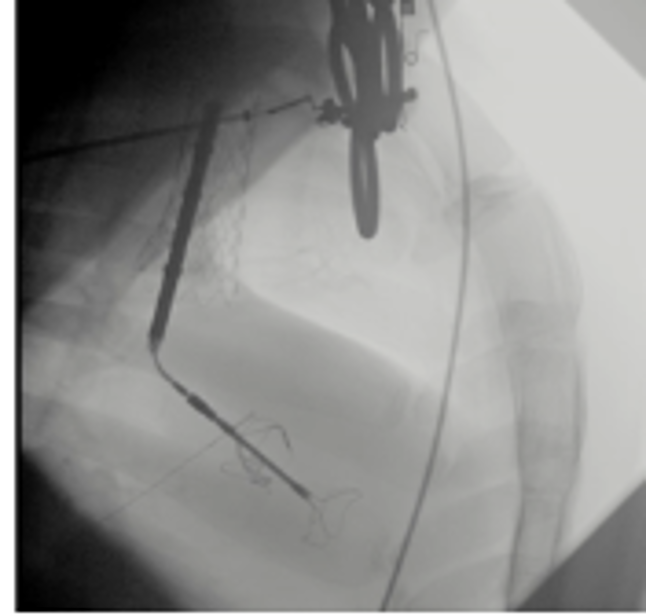

INNOVATIVE TECHNOLOGY: CroíValve has developed a non-invasive device uniquely tailored to the challenges of the tricuspid valve. Delivered via a catheter through a neck vein, it is positioned between the tricuspid valve leaflets to restore function. An innovative adjustable anchor holds the device in position, and sits away from the fragile heart tissue, avoiding any tissue-penetrating hooks. A robust patent portfolio has been developed to protect this novel approach. The implant procedures takes less than 45 minutes using conventional techniques.

PHASE 2 PROJECT: With H2020 SMEi funding, this Phase 2 Innovation project supported the activities necessary to complete clinical implants and demonstrate safety and efficacy for the device. This included extensive pre-clinical verification and validation testing to refine the device and ensure it was ready for patient implants. Significantly this also included a first in human study of this device in 5 patients that has demonstrated significant symptomatic improvement for these patients, along with a very straightforward procedure verified by multiple users.

WP3 Clinical Evaluation: Completion of a 5patient first in human study to demonstrate the safety, efficacy and ease of use of the device